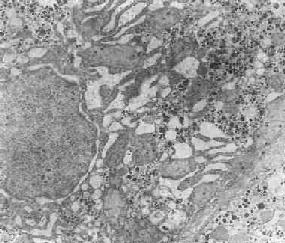

在由各种原因引起的细胞变性和坏死过程中,粗面内 质网的池一般出现扩张,较轻的和局限性的扩张只有在电镜下才能窥见,重度扩张时则在光学显微镜下可表现为空泡形成,电镜下有时可见其中含有中等电子密度的 絮状物。在较强的扩张时,粗面内质网同时互相离散,膜上的颗粒呈不同程度的脱失。进而内质网本身可断裂成大小不等的片段和大小泡(图1-6)。这些改变大 多见于细胞水肿时,故病变不仅见于内质网,也同时累及Golgi器、线粒体和胞浆基质,有时甚至还累及溶解体。

肝细胞粗面内质网扩张

图1-6肝细胞粗面内质网扩张